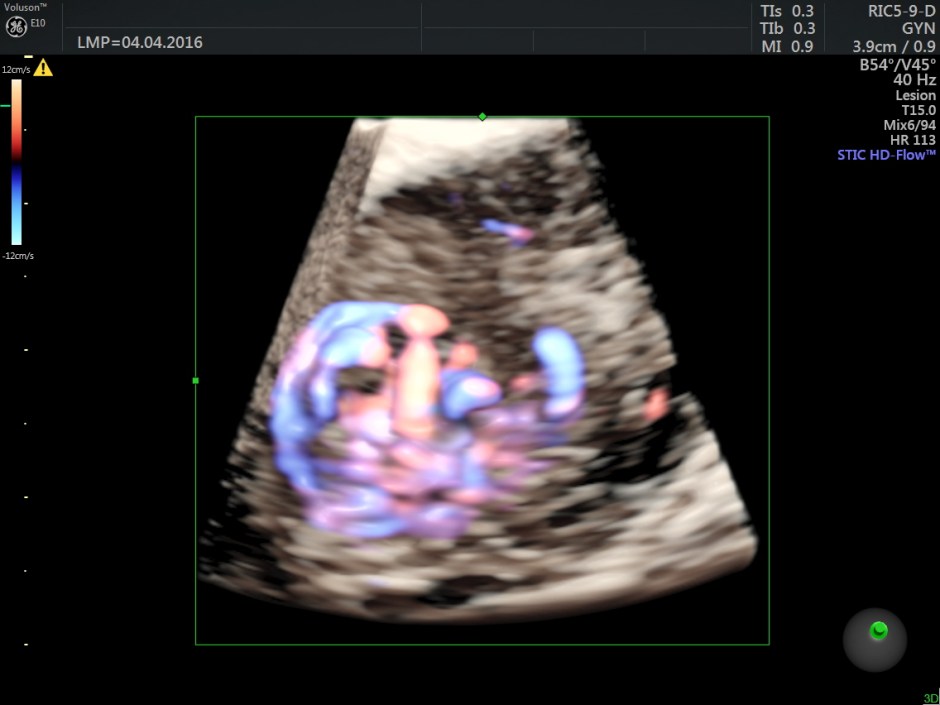

Power Doppler reconstruction images of trans-abdominal scan are given below

The following are the different sections of the Power Doppler reconstruction images of the trans-vaginal scan.

The following are the reconstructed 3D Power Doppler images.